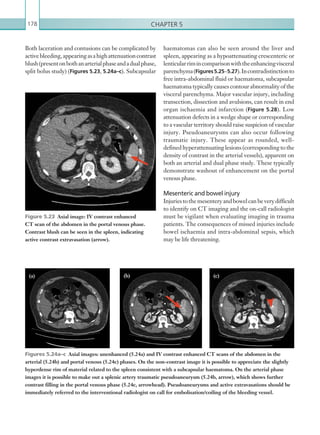

• 91.

Gastrointestinal and genitourinaryimaging 69 Figure 2.61  Sagittal image: IV contrast enhanced CT scan of the abdomen and pelvis in the portal venous phase. The image ­demonstrates locules of free gas within the bowel ­mesentery ­secondary to ­perforated ­diverticulitis. Figure 2.62  Axial image: oral and IV contrast enhanced CT scan of the pelvis in the portal venous phase. A focal abscess can be seen in the mid pelvis as a result of ­localised diverticular perforation. Surrounding inflammatory changes can be seen as a hazy appearance within the adjacent mesentery. Figure 2.63  Axial image: IV contrast enhanced CT scan of the pelvis in the portal venous phase. The image demonstrates diverticulitis with an ­interloop abscess (arrow). Indeterminate cases may ultimately require further evaluation with endoscopy. An important complication of diverticulitis is perforation, confirmed on CT by the presence of free gas (Figure 2.61). This is better appreciated on both lung and bone window settings. Other complications include abscess formation, presenting as a pericolonic fluid-containing focus with or without air and an enhancing wall (Figure 2.62). Interloop abscesses may also occur (Figure 2.63). The size of the abscess is important since this can guide potential treatment. For accessible abscesses, percutaneous radiologically- guideddrainagecanbesuggested.Fistulationcanoccur (suggesting a subacute to chronic course), commonly between the bladder and cervix, and should be suspected in the absence of a clear fat plain between the twostructures.Gaswithinthevaginalvaultandbladder (without prior instrumentation) should also raise the suspicion of fistulation. A thin track of oral contrast can occasionally be seen between the two fistulating K22247_C002.indd 69 16/05/15 3:07 AM

• 92.

Chapter 270 • Themain findings of diverticulitis include the presence of diverticulae, bowel wall thickening and pericolonic fat stranding. • Short segment bowel wall thickening can also be seen in primary colorectal malignancy and should always be considered as an alternative diagnosis. Report checklist • Presence or absence of complications (e.g. abscess formation, perforation, fistulation and post- inflammatory strictures). • Consider the differential diagnosis of underlying colonic malignancy. • Emphasise that in indeterminate cases, direct visualisation via colonoscopy is advised at a clinically appropriate time References Baker M (2008) Imaging and interventional techniques in acute left-sided diverticulitis. J Gastrointest Surg 12:1314–1317. DeStigter K, Keating D (2009) Imaging update: acute colonic diverticulitis. Clin Colon Rectal Surg 22:147–155. structures, confirming the diagnosis (Figure 2.64). Diverticulitis can also be complicated by hepatic abscess formation, appearing as a ring enhancing hypoattenuating focus within the liver (DeStigter Keating, 2009). There is a classification that is intermittently used for staging diverticulitis according to its severity: The Hinchey Classification of Diverticulitis (Table 2.21). This classification is useful in guiding management since localised disease (i.e. stages 1 and 2) is managed conservatively with IV fluid rehydration, IV antibiotics and, if the abscess collections are large, with image- guided percutaneous drainage. Surgical management is recommended for stages 3 and 4, and for patients that do not improve under medical management or have fistula formation. It is also recommended where there is uncertainty as to whether there may be underlying malignancy. Key points • CT is the imaging modality of choice to assess for the presence of, severity and complications of acute diverticulitis. Figure 2.64  Sagittal image: IV and oral contrast enhanced CT scan of the pelvis in the portal venous phase. The image demonstrates the presence of oral contrast in the vaginal vault (arrow). The adjacent loops of sigmoid colon are thickened secondary to acute ­diverticulitis, which has resulted in a colovaginal fistula. Stage 1a Phlegmon. Stage 1b Diverticulitis with pericolic or mesenteric abscess. Stage 2 Diverticulitis with walled off pelvic abscess. Stage 3 Diverticulitis with generalised purulent peritonitis Stage 4 Diverticulitis with generalised faecal peritonitis. Table 2.21 The Hinchey Classification of ­Diverticulitis. K22247_C002.indd 70 16/05/15 3:07 AM

• 93.

Gastrointestinal and genitourinaryimaging 71 cases may warrant urgent surgical intervention. For repeated episodes secondary to gallstones, elective cholecystectomy is often recommended. Emphysematous cholecystitis must be distinguished from simple acute cholecystitis secondary to gallstones. Emphysematous cholecystitis occurs secondary to gas producing organisms such as Clostridium spp. and Escherichia coli and can be rapidly fatal. Urgent diagnosis is vital to facilitate early surgical intervention. Radiological investigations Ultrasound is the imaging modality of choice when acutecholecystitisisclinicallysuspected.Thesensitivity of ultrasound ranges from 80% to 100% and specificity ranges from 60% to 100% (Smith et al., 2009). CT can also be used to diagnose cholecystitis and may be a more appropriate first-line investigation in suspected cases of complicated acute cholecystitis; however, CT is less sensitive than ultrasound for subtle gallbladder wall changes. Plain film imaging can yield signs such as radiopaque gallstones or pneumobilia, but it is not diagnostic. (See Table 2.22.) Radiological findings Ultrasound Findings on ultrasound include gallbladder wall thickening (3 mm), pericholecystic hypoechoic fluid andthepresenceofapositivesonographicMurphysign (Figure 2.65).Gallbladderwallthickeninginisolationis ACUTE CHOLECYSTITIS Acute cholecystitis is the most common acute inflammatory condition of the gallbladder. The vast majority of cases occur secondary to gallstones, usually due to gallstone impaction in the gallbladder neck or cystic duct. A smaller proportion of cases are due to inflammation in the absence of gallstones and these are termed acalculous cholecystitis. Cholecystitis due to gallstones classically occurs in middle-aged women, with obesity being a well- recognised predisposing factor. Acute cholecystitis secondary to gallstones should be differentiated from acalculous cholecystitis, the latter occurring more commonly in critically unwell and paediatric patients without underlying gallstone disease. Symptoms and signs, regardless of the underlying cause, can include right upper quadrant abdominal pain and tenderness, fever and nausea and vomiting. The patient may have a positive Murphy sign, defined as pain on inspiration while palpating the right upper quadrant. Elevated inflammatory markers are a common, but non-specific, associated finding. Complications of acute cholecystitis include abscess formation, pericholecystic fluid collections, gallbladder perforation and enteric fistulation. It is important to identify these complications, since they carryasignificantlyincreasedmortalityrate.Treatment of non-complicated cases is often conservative via appropriate antibiotic therapy; however, complicated MODALITY PROTOCOL Ultrasound 1–5MHz curvilinear probe. CT Post IV contrast, portal venous phase: 100 ml IV contrast, 4 ml/sec via 18G cannula. Scan at 70 seconds. Scan from just above diaphragm to femoral head level. Table 2.22 Acute cholecystitis. Imaging protocol. Figure 2.65  Transverse ultrasonogram of the ­gallbladder. The gallbladder is thick walled with ­surrounding pericholecystic fluid in keeping with acute cholecystitis. K22247_C002.indd 71 16/05/15 3:07 AM

• 94.

Chapter 272 Computed tomography CTfeatures include gallbladder wall thickening (3–5 mm), mural or mucosal hyperenhancement, pericholecystic fluid and adjacent soft tissue inflammatory stranding (Figure 2.66). Gallstones on CT, if visualised, may appear as hyperattenuating (calcified) or hypoattenuating (cholesterol containing) filling defects within the gallbladder lumen. Liver parenchyma adjacent to the gallbladder fossa may also hyperenhance because of reactive hyperaemia. CT is particularly useful in detecting the complications of acute cholecystitis. Specific findings that suggest emphysematous cholecystitis include foci of gas within the gallbladder wall or lumen (Figure 2.67), which can be quickly identified on lung window settings. Features of gallbladder perforation include a focal discontinuity in the gallbladder wall and pericholecystic fluid collections, although the latter can also be seen without gallbladder perforation (Figure 2.68). Other complications include abscess formationaroundthegallbladder.Thismayextendinto the liver, resulting in a liver abscess that may require percutaneous drainage (Figure 2.69). a non-specific finding (Table 2.23) and must always be interpreted with additional sonographic findings and an appropriate clinical history. Gallbladder collapse is a common finding in the post-prandial state. Care must be taken since this can give a false impression of wall thickening. Less specific imaging findings of acute cholecystitis include abnormally increased gallbladder distension and echogenic bile (sludge) within the gallbladder. The presence of sludge, in addition to gallbladder wall thickening in the absence of gallstones, is suggestive of acalculous cholecystitis. Gallstones may or may not be visualised within the gallbladder neck or cystic duct, and they typically appear as echogenic foci with posterior acoustic shadowing. Note: Gallstones are a common incidental finding in asymptomatic patients and their presence does not imply acute cholecystitis. Emphysematous cholecystitis is characterised by gas within the gallbladder wall or lumen, appearing as increased echogenic foci with low-level posterior acoustic shadowing and reverberation artefact. Gallbladder perforation can be challenging to diagnoseonultrasound;however,itshouldbesuspected in the presence of pericholecystic fluid collections or a focal discontinuity in the gallbladder wall. • Cholecystitis. • Hepatitis. • Cirrhosis. • Congestive heart failure. • Hypoalbuminaemia. • Renal failure. • Sepsis. Table 2.23 Causes of gallbladder wall thickening. Figure 2.66  Axial image: IV contrast enhanced CT scan of the abdomen in the portal venous phase. The gallbladder wall is thickened and there is ­adjacent inflammatory fat stranding and free fluid. The ­appearance is consistent with acute cholecystitis. K22247_C002.indd 72 16/05/15 3:07 AM

• 95.

Gastrointestinal and genitourinaryimaging 73 Key points • Ultrasound is the initial imaging modality of choice in the diagnosis of acute cholecystitis. • CT is useful for identifying the complications of acute cholecystitis such as emphysematous cholecystitis and gallbladder perforation. • The hallmark of acute cholecystitis is gallbladder wall thickening, although in isolation this is a ­non-specific finding. Figure 2.67  Axial image: IV contrast enhanced CT scan of the abdomen in the portal venous phase. The gallbladder contains air, as does the gallbladder wall, in keeping with emphysematous cholecystitis Figure 2.68  Axial image: IV contrast enhanced CT scan of the abdomen in the portal venous phase. The gallbladder wall is thickened with large volumes of pericholecystic fluid consistent with acute cholecystitis. A defect is seen in the anterior gallbladder wall (arrow), consistent with a gallbladder perforation. Figure 2.69  Axial image: IV contrast enhanced CT scan of the abdomen in the portal venous phase. The medial wall of the gallbladder is indistinct due to local perforation. Low attenuation material is seen within the right lobe of liver, which communicates with the gallbladder. This appearance is therefore consistent with gallbladder perforation leading to liver abscess formation. Report checklist • Presence or absence of gallstones. • Presence or absence of intrahepatic or extrahepatic biliary dilatation, which may imply an impacted gallstone more distally within the biliary system. Reference Smith EA, Dillman JR, Elsayes KM et al. (2009) Cross-sectional imaging of acute and chronic gallbladder inflammatory disease. Am J Roentgenol 192:188–196. K22247_C002.indd 73 16/05/15 3:07 AM

• 96.

Chapter 274 imaged withCT to fully characterise the severity. (See Table 2.24.) Radiological findings Comuted tomography CT readily identifies gas both within the renal parenchyma and the collecting system. Gas can appear macroscopically similar to fat on CT; direct evaluation of Hounsfield units (gas = approximately 1,000; fat = 50 to –160) and evaluation with lung window settings helps to differentiate the two. Streaky or mottled gas in the interstitium of renal parenchyma, radiating from medulla to cortex, is highly suggestive of emphysematous pyelonephritis (Figures 2.70a, b). Gas can also be seen in the perinephric soft tissues and retroperitoneum; the latter signifies a breach of Gerota’s fascia (Figure 2.71). Focal rim enhancement within the affected renal parenchyma can indicate focal abscess formation. Further non-specific signs can also be seen, such as enhancing perinephric fluid collections, unilateral renal enlargement and decreased parenchymal enhancement (the latter should always prompt scrutiny of the corresponding renal artery and vein to assess for thrombus). Hydronephrosis can be seeninassociationwithemphysematouspyelonephritis and should prompt the search for an obstruction in the ureter. Gas that is limited to the collecting system is suggestive of emphysematous pyelitis (Figure 2.72), although this can also be seen in ureteric fistulation with bowel (secondary to inflammatory bowel disease or malignancy) or pre-existing ileal conduit formation. The ureters should be traced distally to ensure that this is not the case. EMPHYSEMATOUS PYELONEPHRITIS Emphysematous pyelonephritis is a severe, life- threatening infection of the renal parenchyma by gas forming organisms. Approximately 70% of cases are secondary to Escherichia coli, although other causative organisms such as Klesbiella pneumonia and Proteus mirabilis arealsoseen.Thereisastrongassociationwith diabetes mellitus, which is seen in up to 90% of cases (Joseph et al., 1996). Symptoms and signs include flank pain and fever with a rapid progression to sepsis and profound haemodynamic instability. Palpable crepitus over the affected flank is more specific, although the sensitivity of this sign is low. The mortality rate can be as high as 50% and urgent diagnosis is vital (Grayson et al., 2002). The on-call radiologist should have a high index of suspicion for this condition in any diabetic patient with sepsis of unknown origin. Treatment can be conservative in mild cases, involving prompt antibiotic therapy, fluid resuscitation and drainage of complicating collections. In severe cases that fail to respond to conservative management, nephrectomy may be required. It is important to differentiate true emphysematous pyelonephritis from emphysematous pyelitis, in which gas is limited to the renal collecting system. The latter is also associated with diabetes mellitus infection, but carries a much better prognosis; as such, these cases are often managed conservatively. Radiological investigations CT is the initial imaging modality of choice in cases where emphysematous pyelonephritis is strongly suspected. CT is both sensitive and specific and in addition can identify alternative causes of abdominal pain. Although abdominal plain films are usually one of the first radiological investigations performed in any patient presenting with abdominal pain, the sensitivity of this modality for the changes of emphysematous pyelonephritis is low. Renal ultrasound can be an appropriate initial investigation to perform in patients presentingwithflankpaininordertolookforalternative pathologies; however, it is user dependent, technically challenging in larger patients and not as sensitive as CT for emphysematous pyelonephritis. Ultrasound can also underestimate the extent of renal parenchymal involvement, therefore suspected cases should also be MODALITY PROTOCOL CT Post IV contrast, portal venous phase: 100 ml IV contrast, 4 ml/sec via 18G cannula. Scan at 70 seconds after initiation of injection. Scan from just above diaphragm to femoral head level. Table 2.24 Emphysematous pyelonephritis. Imaging protocol. K22247_C002.indd 74 16/05/15 3:07 AM

• 97.

Gastrointestinal and genitourinaryimaging 75 Figures 2.70a, b  Axial and coronal images: IV contrast enhanced CT scans of the abdomen in the portal venous phase. Gas is seen within the left renal parenchyma and there is heterogeneous parenchymal enhancement. Figure 2.71  Axial image: IV contrast enhanced CT scan of the abdomen in the portal venous phase. ­Abnormal left renal parenchymal gas and enhancement is once again shown. There is further retroperitoneal free gas and fluid. Figure 2.72  Axial image: unenhanced CT scan of the abdomen. Locules of gas are seen within the left renal collecting system and upper ureter. (a) (b) K22247_C002.indd 75 16/05/15 3:07 AM

• 98.

Chapter 276 should beactively excluded. In the presence of diffuse retroperitoneal gas, the kidney can be difficult to visualise (Figures 2.74a. b). Abdominal plain film imaging Abdominalplainfilmscandemonstrateabnormallucent gas collections. The diagnosis is suggested by mottled lucencies overlying the renal outlines, which may also correspond to the outline of the renal pyramids. Curvilinear lucencies may indicate subcapsular or perinephric gas. Retroperitoneal gas is indicated by increased definition of the psoas shadows, representing a gas–muscle interface. Note: Retroperitoneal gas is not specific for emphysematous pyelonephritis and can also be seen in perforation of retroperitoneal bowel (duodenum, ascending colon, descending colon and rectum). Key points • Emphysematous pyelonephritis is a life- threatening infection of the kidney and should be suspected in any diabetic patient presenting with flank pain or sepsis of unknown origin. • CT is the most sensitive and specific radiological investigation. Emphysematous pyelonephritis is confirmed when gas is identified in the renal parenchyma, whereas in emphysematous pyelitis, the gas is limited to the collecting system only. Various systems have been proposed to stage the spectrum of findings seen in emphysematous pyelonephritis and pyelitis; these have prognostic importance (Tables 2.25 and 2.26: Huang Tseng, 2000; Wan et al., 1996). Emphysematous cystitis is a rare separate entity where a gas forming infection occurs in the bladder wall. It may be caused by bacterial or fungal infections with E. coli being the most common causative agent (Figure 2.73) Ultrasound Gas within the renal parenchyma has the appearance of high-amplitude echogenic foci, commonly with associated reverberation artefact and comet tail ‘dirty’ shadowing. Calculi can also give a similar appearance, although they characteristically produce more uniform posterior acoustic shadowing. Hydronephrosis Class 1 Gas limited to collecting system. Class 2 Gas limited to renal parenchyma (without ­extrarenal extension). Class 3a Extension of gas or abscess to perinephric space. Class 3b Extension of gas or abscess to pararenal space. Class 4 Bilateral emphysematous pyelonephritis or solitary kidney with emphysematous pyelonephritis. Table 2.25 Emphysematous pyelonephritis. Huang–Tseng CT classification system. Type 1 Renal parenchymal destruction with streaky or mottled appearance of gas. Intra- or extrarenal fluid collections are ­characteristically absent. Type 2 Renal or extrarenal collections associated with bubbly or loculated gas, or gas within the ­collecting system or ureter. Table 2.26 Emphysematous pyelonephritis. Wan et al. classification system. Figure 2.73  Axial image: IV contrast enhanced CT scan of the abdomen and pelvis in the portal venous phase. There are multiple locules of gas within the bladder wall, consistent with ­emphysematous cystitis. K22247_C002.indd 76 16/05/15 3:07 AM

• 99.

Gastrointestinal and genitourinaryimaging 77 Huang JJ, Tseng CC (2000) Emphysematous pyelonephritis: clinicoradiological classification, management, prognosis, and pathogenesis. Arch Intern Med 160:797–805. Joseph RC, Amendola MA, Artze ME et al. (1996) Genitourinary tract gas: imaging evaluation. Radiographics 16:295–308. Wan YL, Lee TY, Bullard MJ et al. (1996) Acute gas- producing bacterial renal infection: correlation between imaging findings and clinical outcome. Radiology 198:433–438. Report checklist • Distinguish between emphysematous pyelitis and emphysematous pyelonephritis. • Presence or absence of adverse prognostic features, such as breach of Gerotas fascia and pararenal collections. • Emphasise urgent surgical review. References Grayson DE, Abbott RM, Levy AD et al. (2002) Emphysematous infections of the abdomen and pelvis: a pictoral review. Radiographics 22:543–561. Figure 2.74a, b  Ultrasonograms of the kidney. Cortical echogenicity is seen in the interpolar region of the kidney, representing parenchymal gas, resulting in an irregular acoustic shadow, which obscures the normal renal contour. (a) (b) K22247_C002.indd 77 16/05/15 3:07 AM

• 100.

Chapter 278 Radiological investigations Thefirst-line investigation for suspected hydronephrosis is ultrasound. Once the presence of hydronephrosishasbeenconfirmed,CTisthemodality of choice for establishing the cause. (See Table 2.27.) Radiological findings Ultrasound Ultrasound of both flanks should be performed to identify both kidneys. Size, corticomedullary differentiation (CMD) and cortical thickness of the kidneys should be assessed. The pelvicalyceal system should be examined in transverse and longitudinal planes; a dilated system indicates hydronephrosis (Figure 2.75). Quantification of hydronephrosis is subjective,butsomecategorisationintomild,moderate or severe should be made. Cortical thickness can be an indicator of the chronicity of renal disease. In the context of hydronephrosis, a thinned renal cortex suggests that the hydronephrosis is long-standing (in the absence of pre-existing renal disease). Parapelvic cysts should not be confused for hydronephrosis. The proximal ureter should be assessed for hydroureter. The bladder should ideally be full and examinedforthepresenceoftransitionalcellcarcinoma (TCC) as a cause for obstruction. The distal ureters can also be assessed here. Bladder outflow obstruction can often cause prominence of the pelvicalyceal system bilaterally. This can be assessed by asking patients to empty their bladder and rescanning both kidneys to assess for any changes in the degree of dilatation. HYDRONEPHROSIS Hydronephrosis is defined as dilatation of the drainage system of the kidney (calices, infundibula and renal pelvis). The term ureterohydronephrosis, or hydroureter, is used when the dilatation also involves the ureters. Hydronephrosis can be acute or chronic, unilateral or bilateral, physiological or pathological. Hydronephrosis can be due to obstructive or non- obstructive causes. Obstructive uropathy refers to the functional or anatomical obstruction of urinary flow at any level of the urinary tract. Obstructive nephropathy is present when the obstruction causes functional or anatomical renal damage, usually manifesting as a decrease in GFR. Hydronephrosis in young adults is most commonly due to renal tract calculi, while in older adults, prostatic hypertrophy/carcinoma, gynaecological malignancies, retroperitoneal or pelvic neoplasms and calculi are the main causes. Clinical features may include back/flank pain, haematuria, retention, fever and deranged renal biochemistry(creatinineandGFRspecifically).Incases of acute hydronephrosis, correction of the obstruction usually returns the renal function to normal levels. Complications or non-treatment can lead to infection orpyonephrosis,chronicobstructionor,lesscommonly, perforation of the urinary tract leading to peritoneal urine leak (urinoma). MODALITY PROTOCOL Ultrasound Curvilinear probe 1–5MHz. CT Non-contrast, nephrographic phase and delayed phase CT post IV contrast: initial scan unenhanced. 100 ml IV contrast via 18G cannula, 4 ml/sec. Scan at 120 seconds (nephrographic phase) and 12 minutes (delayed phase). Scan from above diaphragm to femoral head level. Table 2.27  Hydronephrosis. Imaging protocol. Figure 2.75  Ultrasonogram of the right kidney in the longitudinal plane. The renal pelvis and intrarenal calyces are dilated and contain anechoic fluid. K22247_C002.indd 78 16/05/15 3:07 AM

• 101.